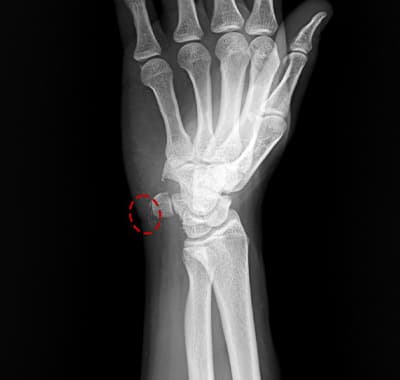

X線・超音波・MRIで石灰の位置・大きさ・密度を確認。石灰の段階(形成期/静止期/吸収期)を判定します。